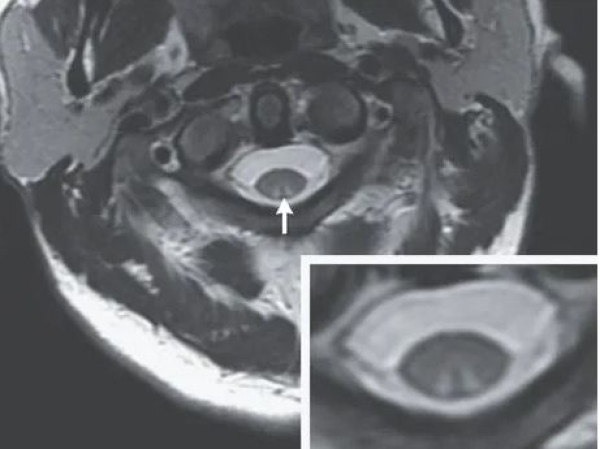

وكشف فحص التصوير بالرنين المغناطيسي أن الحبل الشوكي بدأت تظهر عليه علامات حالة عصبية تعرف باسم اعتلال النخاع، والذي يحدث أحيانا بسبب نقص فيتامين B12، ويحدث هذا عندما يتم ضغط الحبل الشوكي بسبب الالتهاب في المناطق المحيطة.

وإذا ترك دون علاج، يمكن أن يؤدي اعتلال النخاع إلى تلف كبير ودائم في الأعصاب بما في ذلك الشلل وحتى الموت، حيث وجد الأطباء أيضا أن جزءا من النخاع الشوكي، والعمود الظهري، المسؤول عن الشعور باللمس، قد أصيب بجروح بالغة، وكشفت الفحوصات عن وجود آفة متطورة.